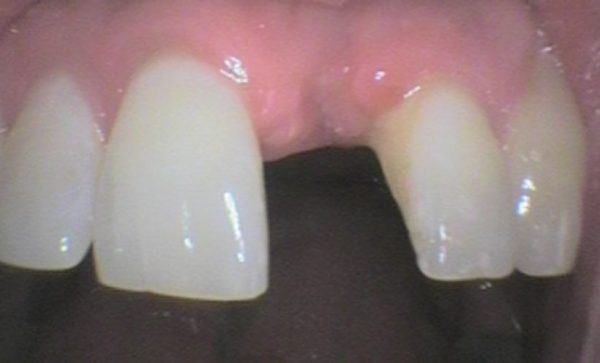

Case 21